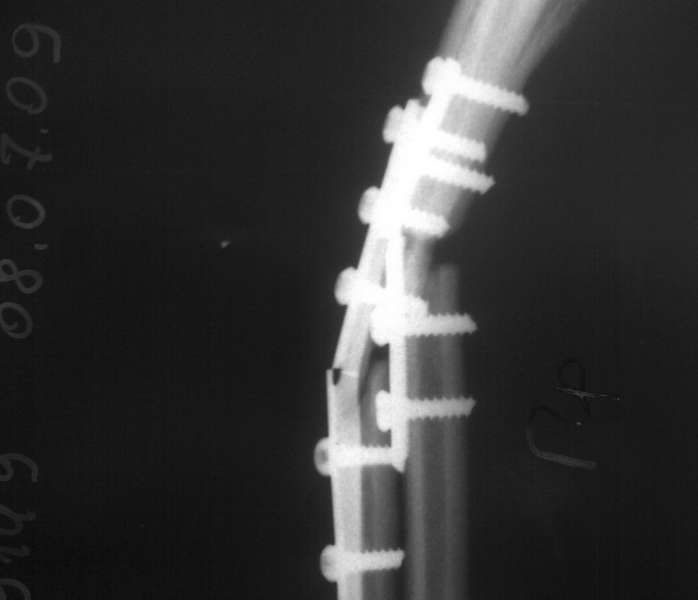

Пациентка С. 23 лет. В марте 2009 года операция остеосинтез костей предплечья пластинами по

поводу оскольчатого перелома. 04.07.09. при совершении супинационных движений

предплечья ощутила хруст (низкоэнергетическая травма). На рентгенограммах несросшийся

перелом костей предплечья, перелом конструкций. Коллеги подскажите что делать,

поделитесь опытом.